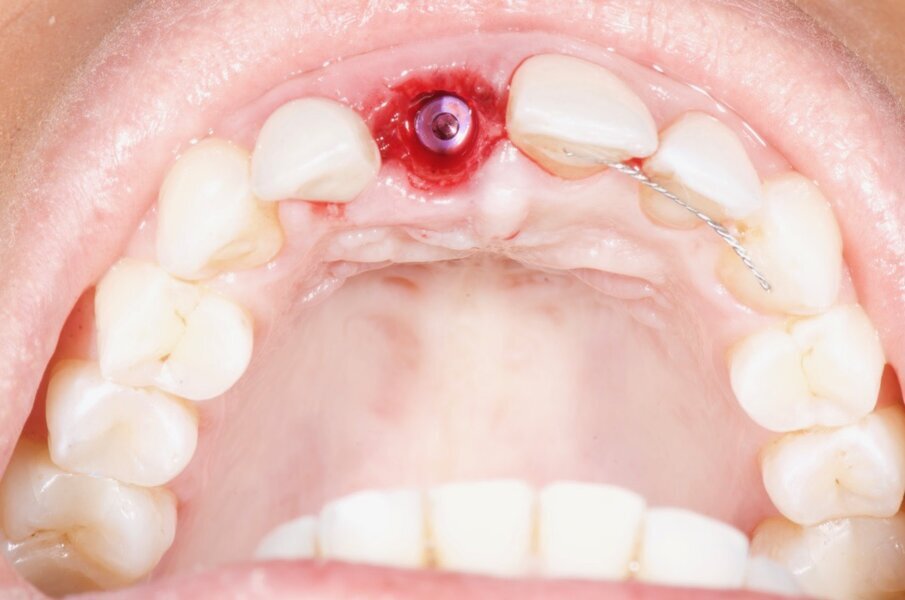

The socket shield technique was planned for this case. Vertical root sectioning was done, removing the palatal part of the root and leaving the facial section intact. Another CBCT scan was taken, and it showed the guide pin in place (Fig. 19). The implant was placed without flap elevation (Fig. 20), and bone substitute was placed to fill the gap (Fig. 21). A screw-retained provisional restoration was placed immediately after implant placement to guide the periodontal tissue healing (Fig. 23). Four months after the procedure, the definitive screw-retained restoration was placed, and very satisfying aesthetic and functional results were evident (Fig. 24).

Fig. 20: Vertical sectioning of the root and atraumatic extraction of the palatal half in the socket shield technique and placement of the implant into site #21.

Fig. 21: Clinical view showing the intact root serving as a buccal shield, the implant in place and the gap to be filled with bone substitute material.

Fig. 22: Intra-oral view three months after the procedure showing the emergence profile.